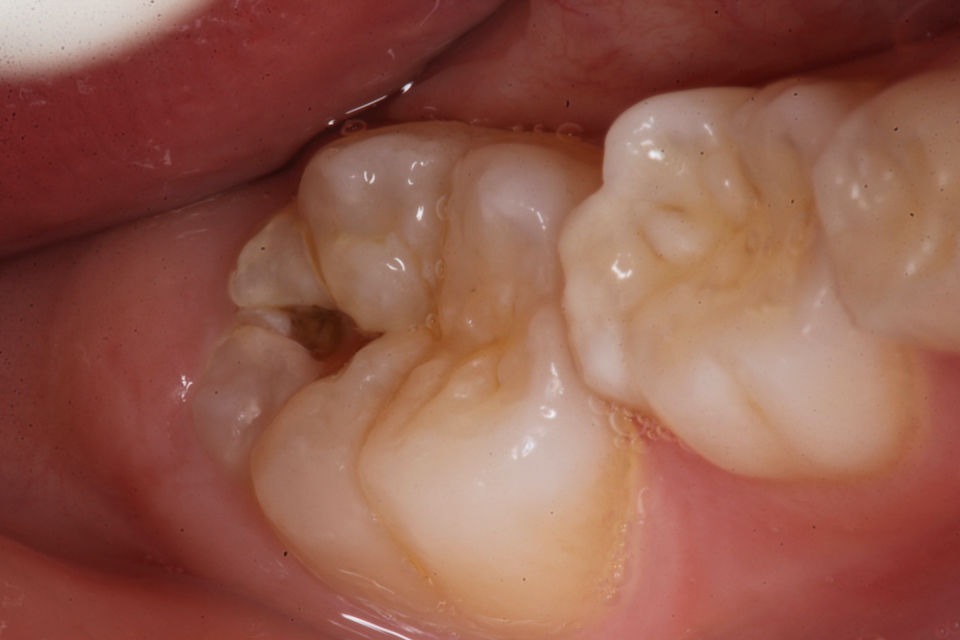

若い子の歯科治療シリーズ1.8(頬側面カリ… 2025.09.20